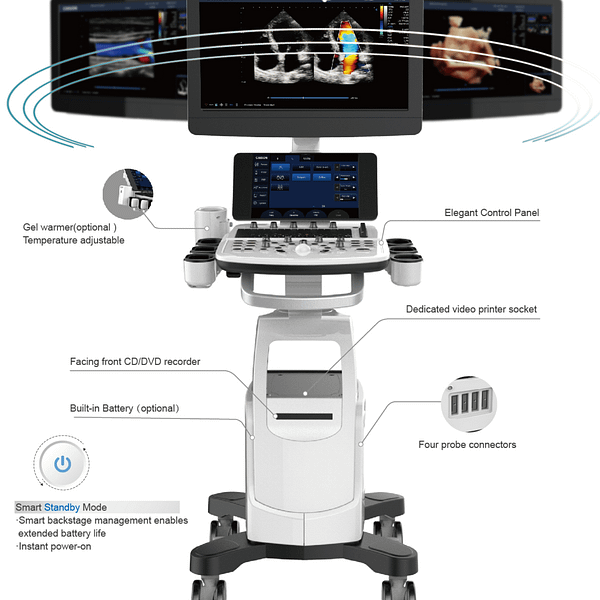

Thiết kế gọn nhẹ:

– Đèn LED HD rộng 21,5 inch

– Màn hình cảm ứng được khách hàng hóa 10,1 inch

– Bốn đầu nối đầu dò

– Máy làm ấm gel

– Có thể điều chỉnh độ cao

- Thiết Kế Gọn Nhẹ và Hiện Đại: Với màn hình LED HD rộng 21,5 inch và màn hình cảm ứng 10,1 inch, CBit 9 không chỉ mang lại trải nghiệm thú vị mà còn đảm bảo sự tiện lợi và linh hoạt trong sử dụng.